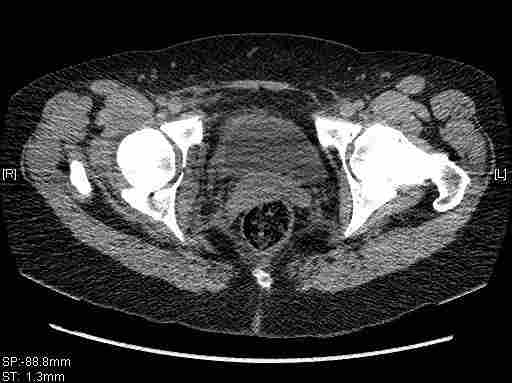

Женщина,58 лет, после ДТП 6 суток. Первично повреждение расценено как переломы ветвей лонной кости. После подтверждения повреждения вертлужной впадины,как чаще всего случается, вопрос встал о тактике. БОльшинство за консерватиное лечение.К сожалению кт у нас "во время" сломался. Прилагаю стандартные снимки вертлужки. У меня следующие вопросы к коллегам:1. Правильно ли рассценивать это повреждение как Т-образный перелом вертлужнй впадины?2. Можно ли добиться анатомической репозиции поверхности вертлужной впадины скелетным вытяжением в данном случае, если нет, что будет этому препятствовать?3. Если смещение останется таким как сейчас, через какое время появится необходимость эндопротезирования (по вашему опыту)?Спасибо.

Удалось сегодня вывести пациентку в соседнюю больницу, где есть кт. Срезы сделаны только горизонтальные.

|

Приветствую,Антон.Рункова рядом нет,но после полученных данных КТ,обсуждали совместно.Итог обсуждения-развернутый ответ дать не получится,т.к.срезы выбраны не информативные.Если ориентироваться на данные 3D,то ,ИМХО,можно лечить на вытяжении.